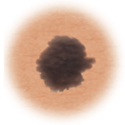

Melanoma

Skin cancer showing more than one color.

Color

When the mole has more than one color